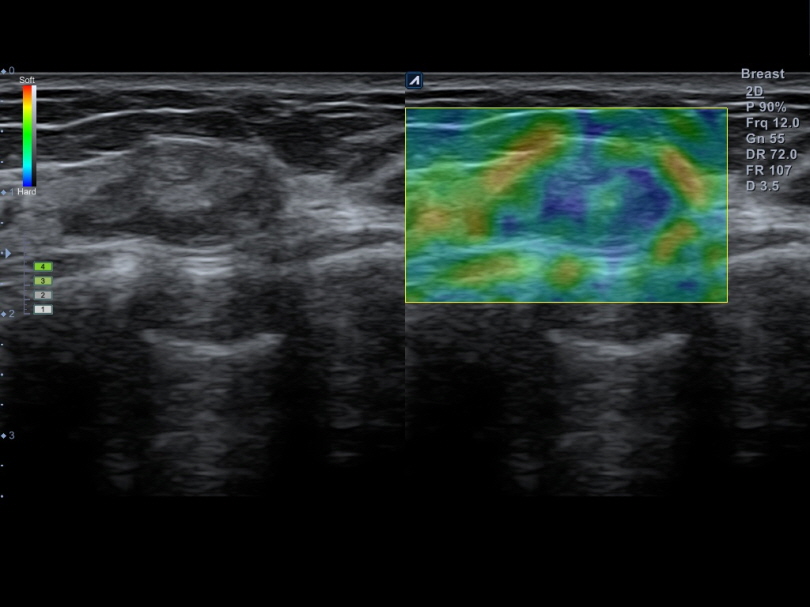

L8-17H

High density linear transducer(8-17MHz)

Application:

Breast, EM, MSK, Vascular, Small Parts

L3-12H

High density linear transducer (3-12MHz)

Application:

Breast, EM, MSK, Vascular, Small Parts

L3-12HWD

High density wide footprint linear transducer (3-12MHz)

Application:

Breast, EM, MSK, Vascular, Small Parts, Appendix

L3-12T

Linear transducer (3-12MHz)

Application:

Breast, EM, MSK, Vascular, Small Parts, Appendix